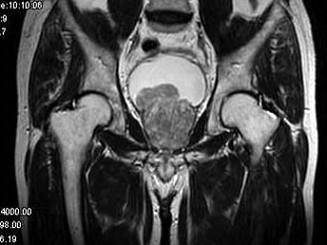

问题 男,60岁。尿频,淋漓不尽半年余。MRI扫描见前列腺明显增大并突入膀胱,最可能的诊断是 ( )

选项 A、膀胱乳头状瘤 B、未见异常 C、前列腺癌 D、膀胱癌 E、前列腺增生

答案 E